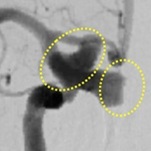

脳動脈瘤コイル塞栓術(血管内治療)

治療前(血管造影画像)

治療後(血管造影画像